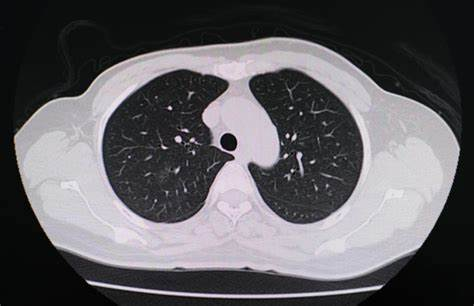

近期,国内多地爆发儿童“白肺”疫情,引起了社会各界的广泛关注。“白肺”是重症肺炎在X光检查下的一种表现,肺部显影呈一大片白色状,这往往预示着肺部被炎症严重侵润,病情危急。而此次疫情中,支原体耐药性问题成为了一个突出的焦点,给儿童的治疗带来了极大的挑战。

“白肺”患儿通常会出现持续高热、咳嗽、喘息、呼吸困难等症状。病情严重时,还可能引发肺不张、胸腔积液等并发症,甚至危及生命。以一名7岁患儿为例,该患儿出现高热伴咳嗽,在家附近的社区卫生服务站给予“阿奇霉素针”输液治疗6天,病情一直未见好转,仍反复高热,咳嗽逐渐加重,精神也变差。经肺部CT检查,提示右肺炎症,右肺中叶肺不张,右侧胸腔积液,最终被确诊为“重症肺炎、胸腔积液、肺不张”。